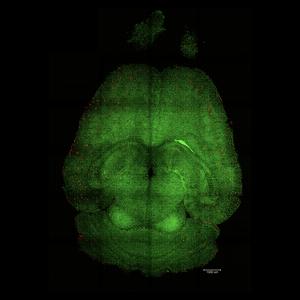

Credit: Institute for Bioengineering of Catalonia (IBEC)

Un equipo de investigación codirigido por el Instituto de Bioingeniería de Cataluña (IBEC) y el Hospital West China de la Universidad de Sichuan (WCHSU) en colaboración con investigadores del Reino Unido, ha demostrado una estrategia basada en nanotecnología que revierte la enfermedad de Alzheimer en ratones. A diferencia de la nanomedicina tradicional, que se basa en nanopartículas como portadoras de moléculas terapéuticas, este enfoque emplea nanopartículas que son bioactivas en si mismas: "fármacos supramoleculares". En lugar de dirigirse directamente a las neuronas, la terapia restaura la función adecuada de la barrera hematoencefálica (BBB por sus siglas en inglés), el “guardián vascular” que regula el entorno del cerebro. Al reparar esta interfaz crítica, los investigadores lograron revertir la patología del Alzheimer en modelos animales.

El cerebro es el órgano más caro del cuerpo, consumiendo el 20% de la energía en adultos y hasta el 60% en niños. Esta energía llega a través de un vasto suministro de sangre, asegurado por un sistema vascular único y denso donde cada neurona se nutre de un capilar. Nuestro cerebro contiene aproximadamente mil millones de capilares, lo que destaca el papel vital del sistema vascular cerebral en el mantenimiento de la salud y la lucha contra las enfermedades. Estos hallazgos resaltan el papel crucial de la salud vascular, especialmente en enfermedades como la demencia y el Alzheimer, que se relacionan con un sistema vascular comprometido.